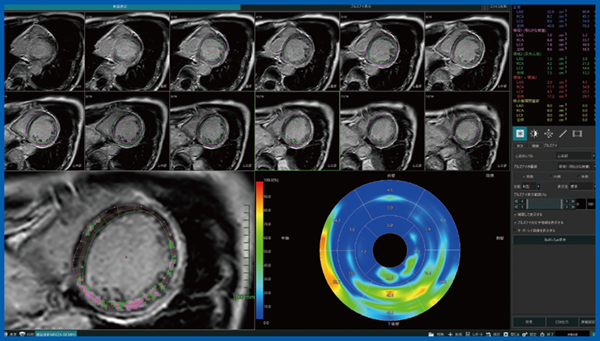

拡張型心筋症や肥大型心筋症における心筋の淡い線維化は,LGE MRIにて心筋梗塞ほど明瞭に描出されないが,カットオフ値を設定することでAbierto Visionで評価可能である(図2)。

図2 LGE定量解析:拡張型心筋症